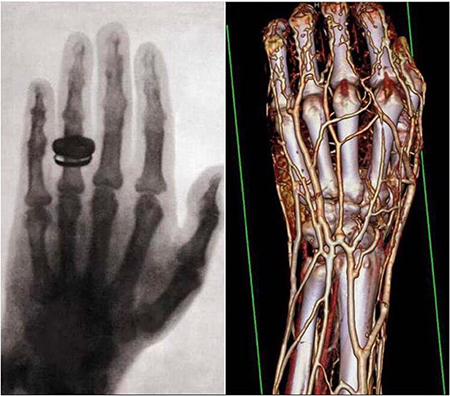

The fundamental research on the physics of elementary particles and nature's fundamental forces led to numerous spin-offs and has tremendously helped human well-being and health. Prime examples include the electron-based generation of x-rays for medical imaging, the use of electrical shocks for treatment of heart arrhythmia, the exploitation of particle's spin momenta for spin tomography (NMR) of patients, and the application of particle beams for cancer treatment. Tens of thousands of lives are saved every year from the use of those and other physical principles. A strong industry has developed in many countries, employing hundreds of thousands of physicists, engineers, and technicians. Industry is designing, producing, and deploying the technology that is based on advances in fundamental physics.